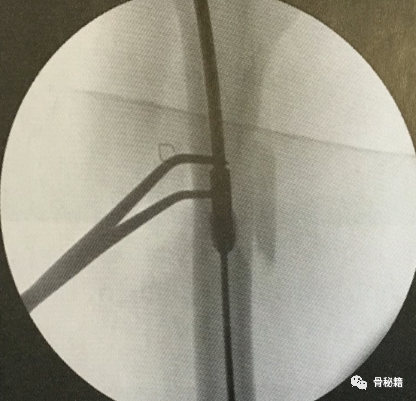

6最后提一点锁钉的小技巧,不要造成主任打主钉5分钟,我们锁钉2小时。我们透视的时候,要把锁定空透成两个圆形,但是在操作中往往是椭圆形,这个时候根据椭圆形的长轴来方向来移动C臂,就可以透一个好的圆形了,在此情况下完成锁钉就相对容易些。